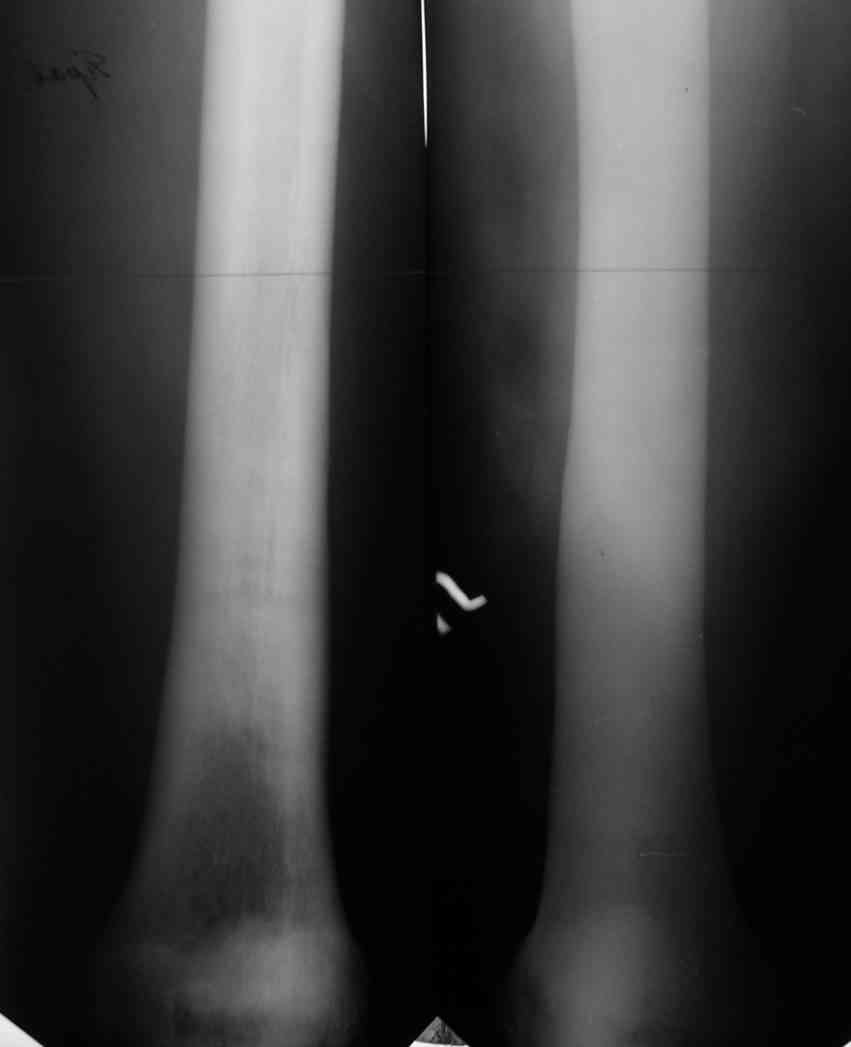

Уважаемый Константин Иванович! Полностью согласен с проф. Михайловым, данный случай не похож на мраморную болезнь, при которой имеется резкое, строго симметричное и генерализованное уплотнение костной ткани (остеопетроз), и кость оказывается построенной преимущественно из гомогенного компактного костного вещества. Для примера привожу случай из архива нашего института (бедренные, плечевые кости и таз, рис 1,2,3)